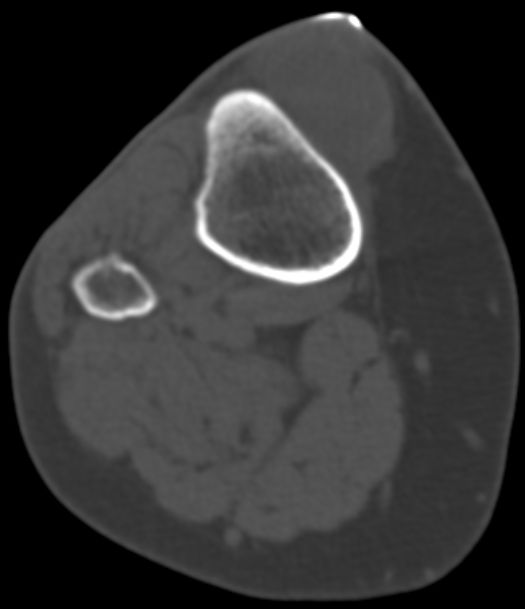

| Fall | CT: Rundliche, kapsulierte, glatt begrenzte RF an der proximalen Tibia medialseitig 3 cm.

Keine Infiltration der Haut oder der Tibia.![]() |